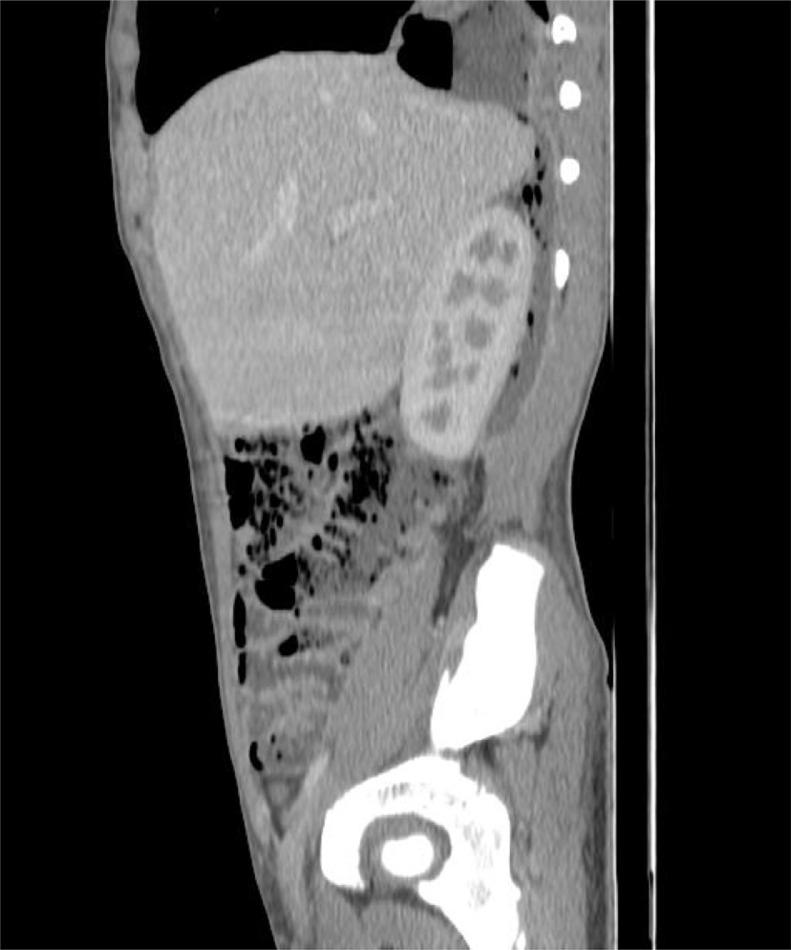

Retrocecal appendicitis usually presents with atypical signs and symptoms which may lead to delayed diagnosis, perforation and serious complications. Development of a large lung abscess secondary to perforation of retrocecal appendicitis in an adolescent patient is an extremely rare entity and to the best of our knowledge has not been described in literature. We present a 15-year-old boy with complaint of chest pain, cough, fever, vague abdominal pain and raised inflammatory markers who underwent CT examination. On CT, a collection with focal calcification was noted in the right iliac fossa that extended along the right retroperitoneum through the retrocrural space in the right lung base communicating with a cavitary pulmonary lesion with air-fluid level. A diagnosis of perforated retrocecal appendicitis with retroperitoneal and right lung abscesses was made. The patient underwent appendectomy and the entire retroperitoneal and lung abscesses were drained. A lung abscess as a complication of perforated retrocecal appendicitis should be in consideration in septic patients with thoracoabdominal infectious manifestations.